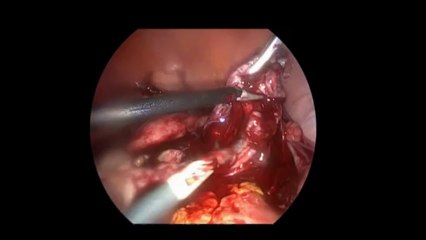

Laparoskopi ile Endometiroma 32 - Prof. Dr. Aydan Biri

Laparoskopi ile Endometiroma 32 - Prof. Dr.